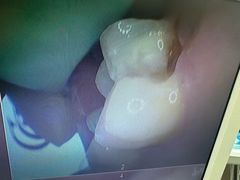

• 牙博士口腔品牌连锁(杨浦店)

• -牙博士口腔品牌连锁(杨浦店)